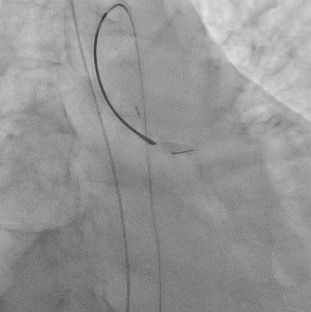

Percutaneous coronary intervention (PCI) was initiated by a right femoral approach using a 7 Fr EBU 3.5 guide catheter. We started from NC balloon and cutting balloon for lesion preparation, then first BMS was deployed successfully but the 3.5 X 48mm DES was hard to push even by side branch and distal anchor technique. We changed our strategy from 1 long stent to 2 shorter stent with a shorter DES and it work. But, due to the jailed LCX orifice, the reversed culotte technique was used with the opened 48mm DES at the beginning as bail out 2 stent strategy. We were able to deployed the opened 48mm DES at the LM-LCX successfully, however, the balloon could not be deflated and was stuck! We hurriedly tried the opened cutting balloon and back-and-forth traction but failed. Even worse, the balloon shaft snapped! We tried to engage the guiding to catch the balloon but failed again. Overall, this was a catastrophe with an un-deflated fractured balloon trapped and stuck at the left main coronary artery.The patient complained of severe chest pain accompanied by a dropping blood pressure. We administered Bosmin with Levophed pump for the shock status and contacted the Cardiovascular surgeon and ECMO team immediately. For our last resort, we tried the Snare to catch the proximal tip of the undeflated fractured balloon and finally we succeeded. We were able to capture the balloon and retrieve it, with the angiography resulted expanded stent with normal coronary flow.

Case Summary

Balloon entrapment is an uncommon complication during PCI. We can try gentle traction if deflation is possible, and advance another guide extensor for retrieval. But if the balloon fails to deflate, with balloon shaft fracture. This is even rare and one of the most dreaded complications, especially at the left main, which can occlude coronary flow, causing myocardial infraction, shock, and even death. If such an unfortunate event occur, stay calm then stabilize the hemodynamics (including vasopressor, IABP, ECMO). Several percutaneous maneuvers (ex. Snare) can be tried, and do not hesitate to contact the surgeons for emergent operation if the efforts fail.